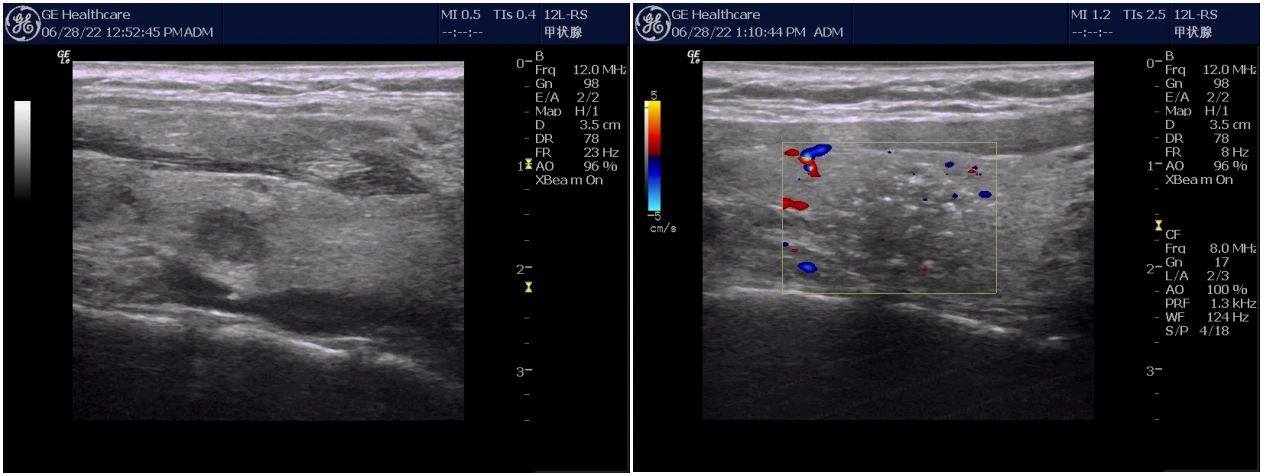

大部分甲状腺结节是在无症状的情况下被发现的,比如拍胸片,CT,MRI或者其他体检,其中绝大部分患者甲状腺功能也是正常的,极少部分会出现轻微甲亢状态。甲状腺结节最简单的检查手段就是触诊,这个办法对于1㎝以上的结节可以,但是对于小于1㎝的,或者结节位置处于下份的小结节来说触诊检查就显得有些力不从心了。当结节病情发展到一定程度,比如结节长大,患者可能会感到颈部疼痛、咽喉部异物感,或者存在压迫感,有些人甚至会发生颈部水肿。目前来讲,甲状腺结节常用的检查方法除了触诊以外,还有彩超,CT,MRI,核素扫描等,其中彩超最简单,方便。

很多人谈“癌”色变,对甲状腺也一样,发现就是“一刀切”;从此过上补充甲状腺激素的日子。随着医学科技的进步,患者有了更多的选择,目前针对甲状腺癌常用的治疗办法有传统外科手术,微创消融,腔镜手术三种。外科手术和腔镜手术严格上来说属于同类治疗办法,唯一区别是有无颈部的瘢痕,但需要面对共同的结果就是大部分人需要终生补充甲状腺激素,也存在喉返神经损伤,周边组织粘连,复发后再次手术困难等问题。对于1㎝及其以下的甲状腺微小乳头癌目前有了新的选择---微创消融,目前常用的消融有微波,射频和激光,其中微波消融应用最广泛,具有术后没有瘢痕,不需要服用甲状腺激素。所以,发现甲状腺癌并不是必须要切除哦。

△消融术前术后比较